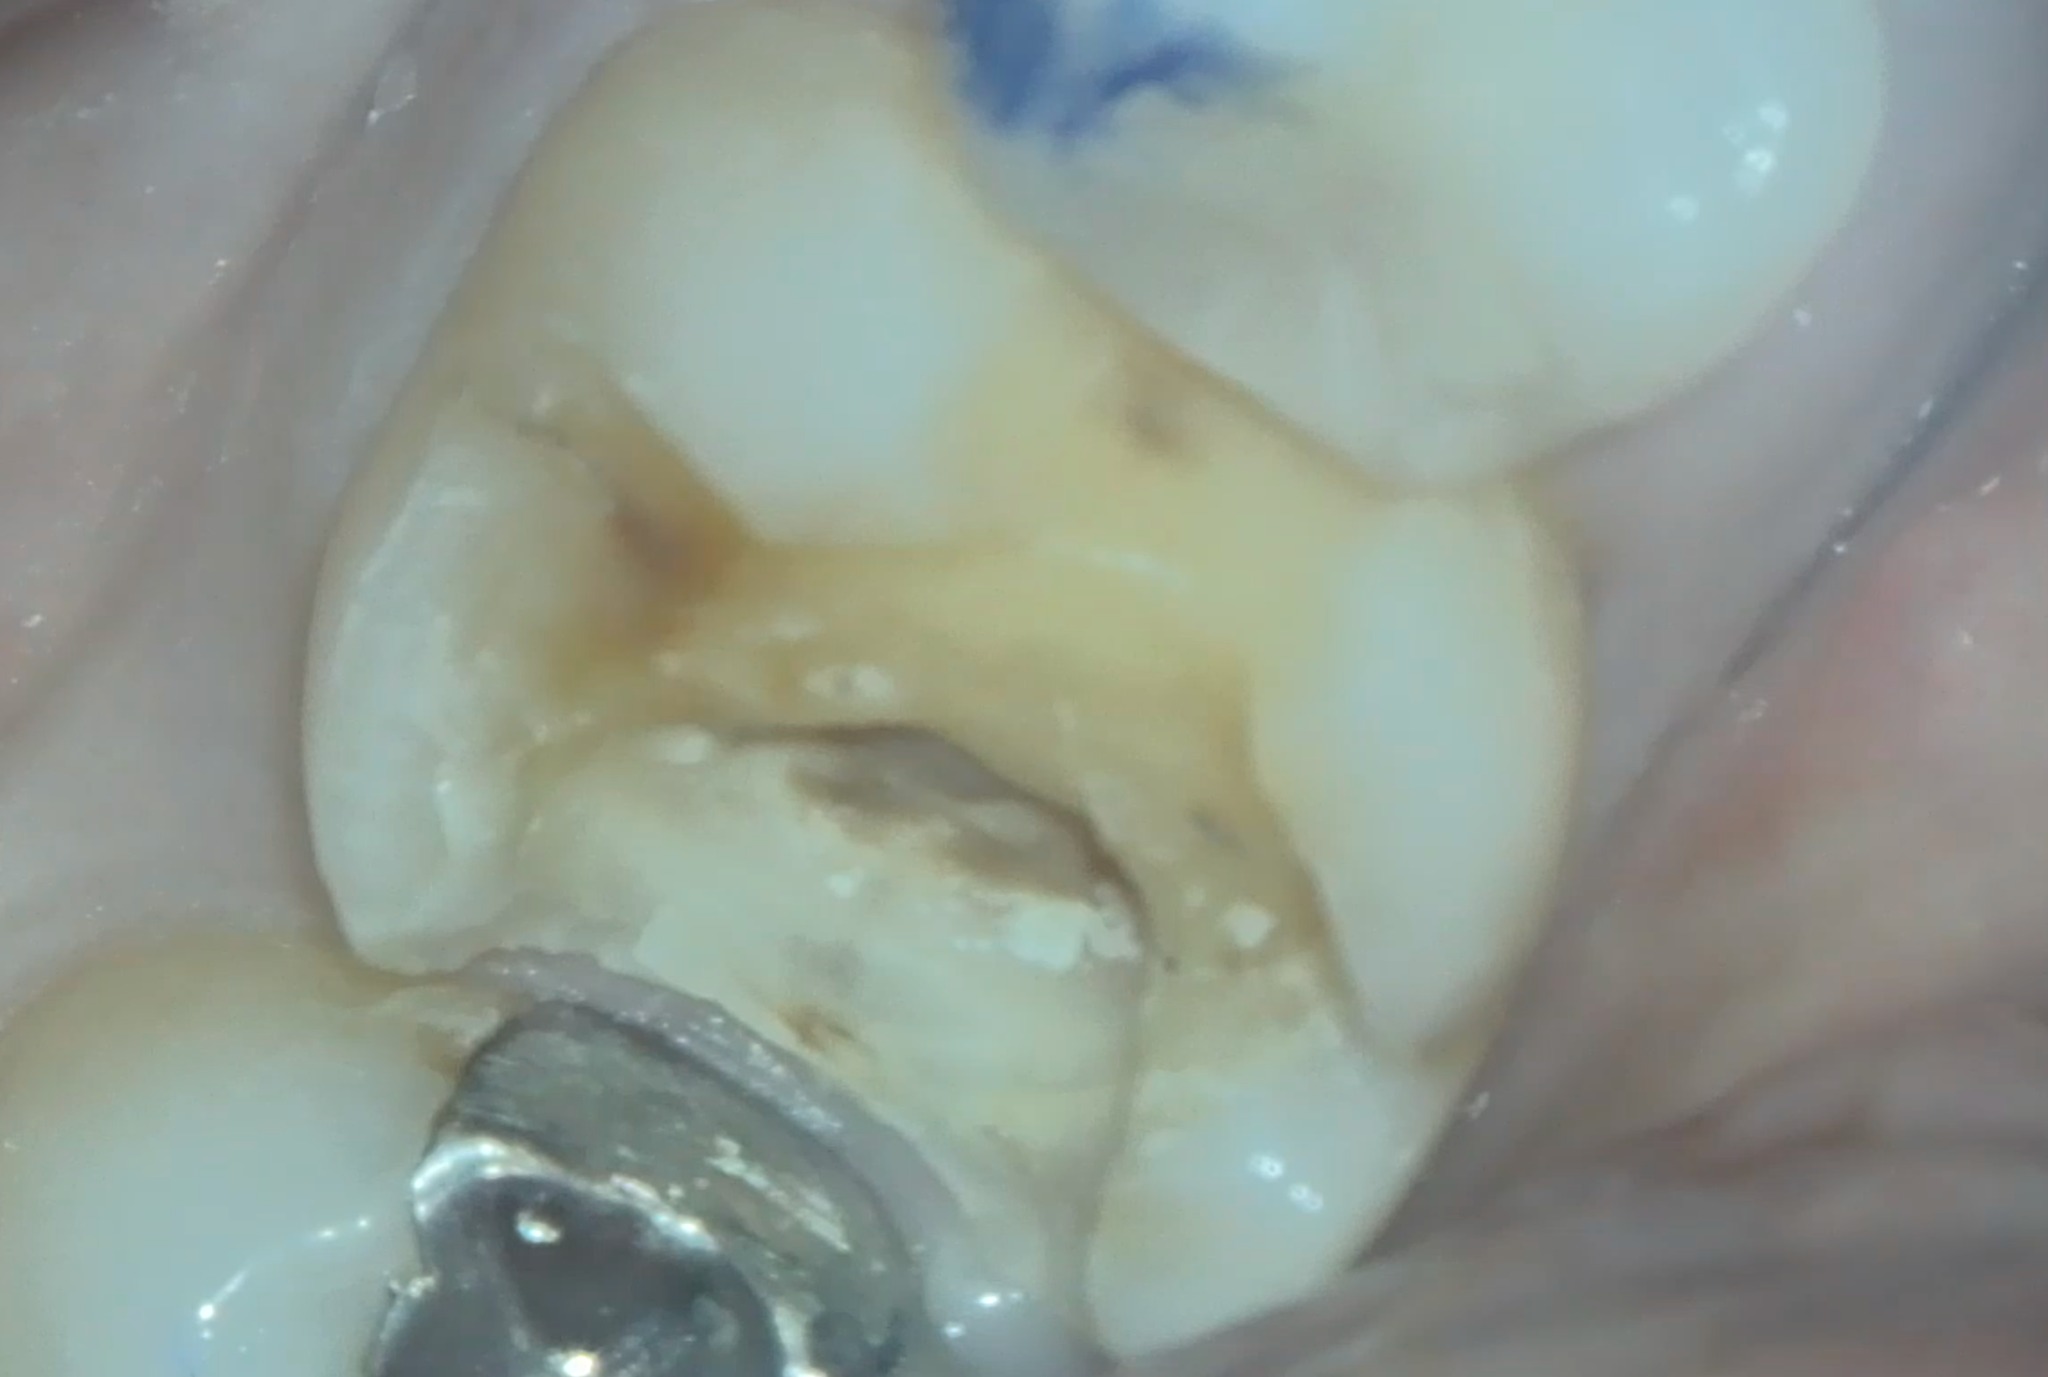

これは「半年前に治療したジルコニアの歯が何か変だ」という主訴で来院された患者さんのお写真です。表面を見るだけでは異常は見られませんでしたが、レントゲン撮影してみると、虫歯が残っているようでした。ご説明の上でジルコニアを外すと、予想以上に大きな虫歯が進行しており神経まで達していました。

赤色は虫歯を発見するための染色剤で、流しても赤く残る部分は虫歯です。虫歯を完全に除去すると、神経が露出してしまいました。